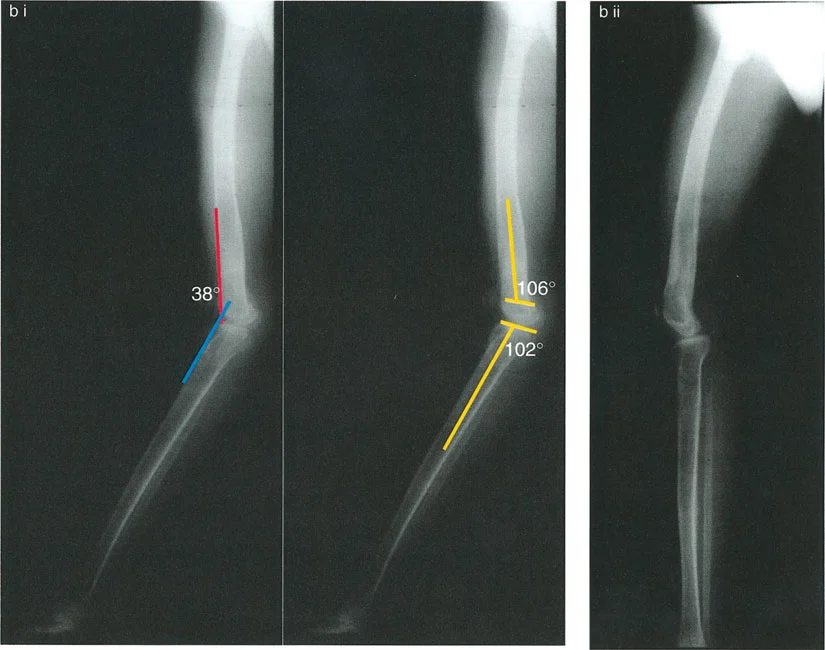

الارتداد الفخذي (Femoral Recurvatum):

- يحدث هذا عندما يكون هناك انحناء مفرط في الجزء السفلي من عظم الفخذ، مما يجعل الركبة تتمدد بشكل مفرط. يمكن أن ينجم عن توقف جزئي في النمو أو تشوهات خلقية.

- على سبيل المثال، قد يؤدي توقف النمو الجزئي في عظم الفخذ البعيد إلى تشوه ارتدادي فخذي بمقدار 20 درجة، مما يسبب فرط تمدد الركبة.

- مريض يعاني من ارتداد فخذي عرضي بسبب شلل الأطفال.

2. التصوير الشعاعي (الأشعة السينية):

تُعد الأشعة السينية ضرورية لتقييم التشوهات العظمية في المستوى السهمي. يتم التقاط صور شعاعية جانبية (Lateral X-rays) للركبة في وضعيات مختلفة (تمدد كامل، انثناء).

زوايا القياس الهامة:

- زاوية الانحناء البعيدة للفخذ (PDFA - Posterior Distal Femoral Angle): تقيس زاوية الجزء السفلي من عظم الفخذ. القيمة الطبيعية حوالي 84 درجة. الزيادة في هذه الزاوية (أكثر من 84 درجة) تشير إلى ارتداد فخذي.

- زاوية الانحناء القريبة للظنبوب (PPTA - Proximal Posterior Tibial Angle): تقيس زاوية الجزء العلوي من عظم الساق. القيمة الطبيعية حوالي 80 درجة. الزيادة في هذه الزاوية (أكثر من 80 درجة) تشير إلى ارتداد ظنبوبي.

- مركز دوران الزاوية (CORA - Center of Rotation of Angulation): يتم تحديد هذا النقطة على الأشعة السينية لتحديد مكان التشوه العظمي بدقة، وهو أمر بالغ الأهمية لتخطيط عملية قطع العظم.

- الركبة الارتدادية بسبب تشوه مركب (فخذي وظنبوبي):

- إذا كان هناك ارتداد في كل من الفخذ والساق، وكان مجموع درجتي الارتداد يساوي درجة فرط التمدد الكلي للركبة.

- إذا كان هناك تشوه مركب مع تقلص انثناء مصاحب، فقد يكون فرط التمدد السريري أقل من مجموع التشوهات العظمية.

- إذا كان هناك ارتداد في كل من الفخذ والساق، وكان مجموع درجتي الارتداد يساوي درجة فرط التمدد الكلي للركبة.